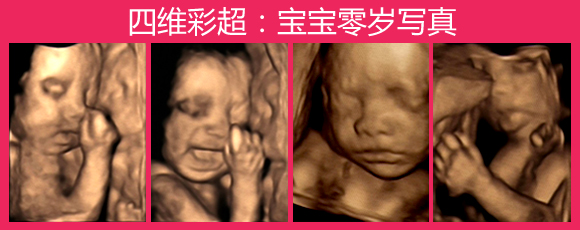

什么是四维彩超

石家庄燕赵妇产医院的专家表示,所谓四维彩超,它主要就是对胎儿畸形,或者胎儿骨骼发育异常,以及心血管畸形等早期诊断。同时还可以在女性宫内,即照出胎儿畸形的照片,较早发现畸形儿,可以及时终止妊娠,预防了畸形胎儿的出生;而且不存在各种辐射,对人体健康没有任何影响,是现在很多孕妇产前检查必要的一项。

石家庄燕赵妇产医院引进高清四维彩超是目前世界上最先进的彩色超声设备。该革命性的技术能够实时获取三维图像,超越了传统超声的限制。可以广泛应用在腹部、血管、小器官、产科、妇科、泌尿科、新生儿和儿科等多领域各个方面。能够显示您未出生的宝宝的实时动态活动图像,为早期诊断胎儿先天性体表畸形和先天性畸形方面提供科学的依据,并能了解胎儿不同发育时期的活动状态、测定胎儿年龄、分析胎儿的发育情况和评价多胞胎或检测胎儿异常等。

四维彩超其绝佳的清晰度、三维立体成像、流畅细腻的画面,都是其他机器无法比拟的。是目前国际上公认的最好的四维彩超仪器。

四维彩超能够多方位、多角度地观察宫内胎儿的生长发育情况,为早期诊断胎儿先天性体表畸形和先天性心脏疾病提供准确的科学依据。